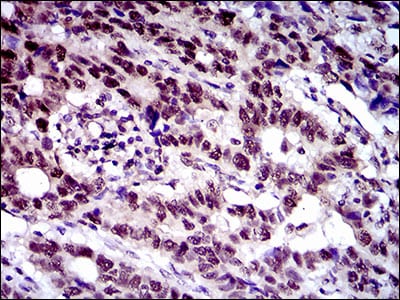

分类: 科研抗体货号: 30518别名: STSL应用: WB,IHC,FCM反应种属: Human

分类: 科研抗体货号: 30523别名:应用: WB,IHC,IF反应种属: Human

分类: 科研抗体货号: 30517别名: CASH; FLIP; MRIT; CLARP; FLAME; Casper; FLAME1; c-FLIP; FLAME-1; I-FLICE; c-FLIPL; c-FLIPR; c-FLIPS; CASP8AP1应用: IHC反应种属: Human

分类: 科研抗体货号: 30522别名: CD25; IL2R; TCGFR; IDDM10应用: WB,IHC,IF反应种属: Human,Mouse,Monkey,Rat